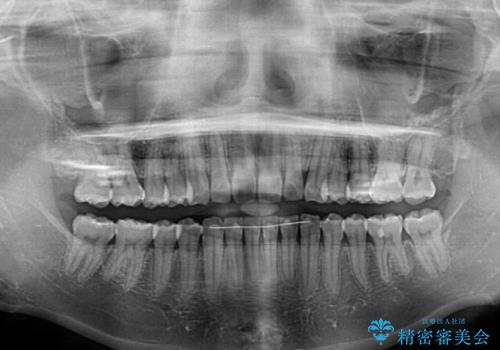

- 上下前歯の叢生を気にして来院された患者様です。

以前矯正をした後戻りということで、歯列不正はそれほど大きくなかったため、インビザライン・ライトを用いて矯正治療を行うこととしました。

前歯のデコボコが残っており、シミュレーション通りに動いていない部分がありましたが、再矯正であることやご本人の満足いくところまでデコボコが改善されたとのことで、治療を終了することとしました。